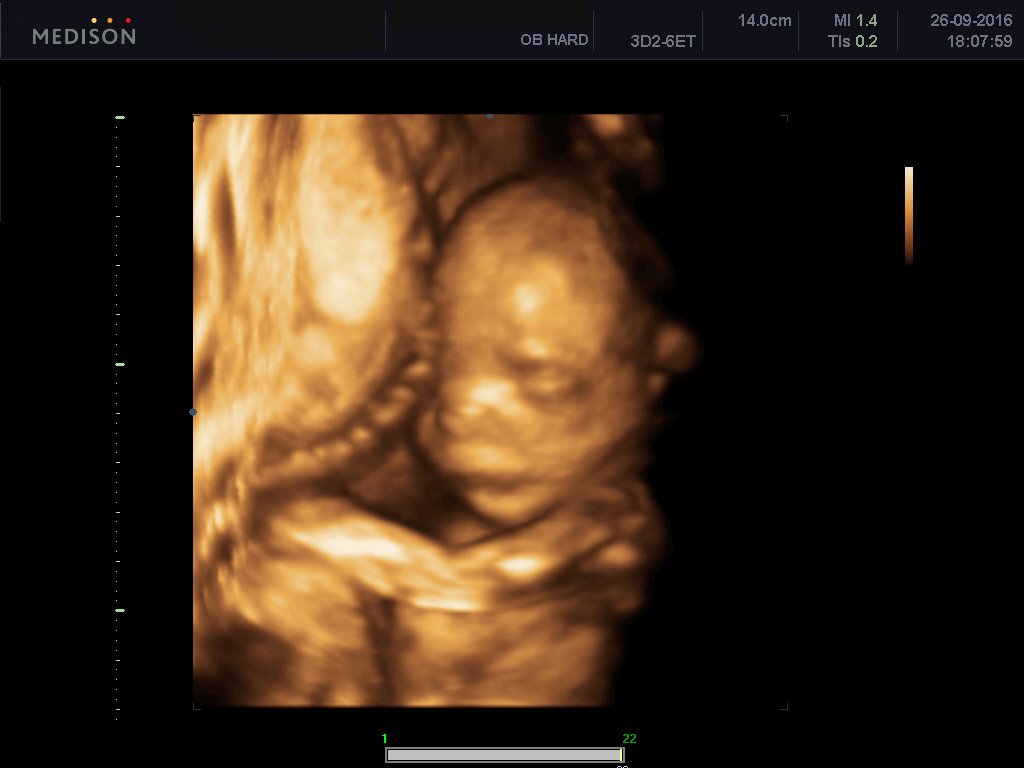

To υπερηχογράφημα (β-επιπέδου) εκτελείται μεταξύ 18ης-22ης εβδομάδας κυήσεως

To υπερηχογράφημα β επιπέδου είναι ειδικό υπερηχογράφημα το οποίο εκτελείται από εξειδικευμένο ιατρό και με το οποίο ελέγχεται λεπτομερώς η ανατομία του εμβρύου. Γίνεται όπως όλα τα υπερηχογραφήματα δια μέσου της κοιλιακής χώρας της εγκύου και είναι απόλυτα ανώδυνο.Είναι δυνατόν το υπερηχογράφημα να απεικονίσει σοβαρές συγγενείς ανωμαλίες του εμβρύου καθώς και ελαφρές ανατομικές βλάβες. Επίσης αναγνωρίζει υπερηχογραφικά σημάδια , τα καλούμενα markers , με τα οποία υποπτευόμαστε σοβαρά χρωμοσωμιακά σύνδρομα εμβρύου, όπως το σύνδρομο Down, την trisomy 18 και trisomy 13. Γίνεται έλεγχος του πλακούντα εκτιμάται το αμνιακό υγρό καθώς και η προβολή του εμβρύου και ο τράχηλος της μήτρας και ειδικά το μήκος τραχήλου μας δίνει πληροφορίες όσον αφορούν τον πρόωρο τοκετό.